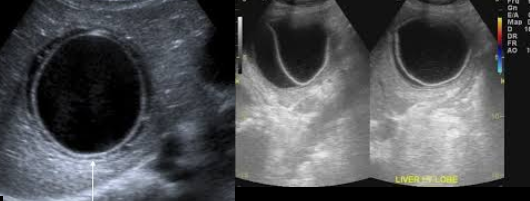

(most commonly) pneumocystis carinii (associated with hepatic granuloma)

hepatic granulomas (associated with pneumocystis carinii)